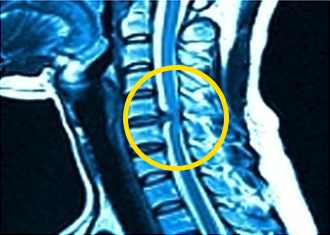

목디스크란 목뼈와 목뼈 사이의 디스크가 손상되어 신경을 압박하는 질환이라고 합니다. 목디스크의 대표적인 증상으로는 어깨통증이 있으며 목에 통증이 먼저 생기고 목과 연결되어 있는 어깨의 신경에 부담이 가해져 어깨 통증이 나타난다고 합니다. 그리고 목디스크에 문제가 생기면 혈액순환 장애가 일어나 어지럼증이 나타날 수 있으며 뒷목이 뻣뻣해지고 쑤시고 결리는 통증을 겪을 수 있습니다.